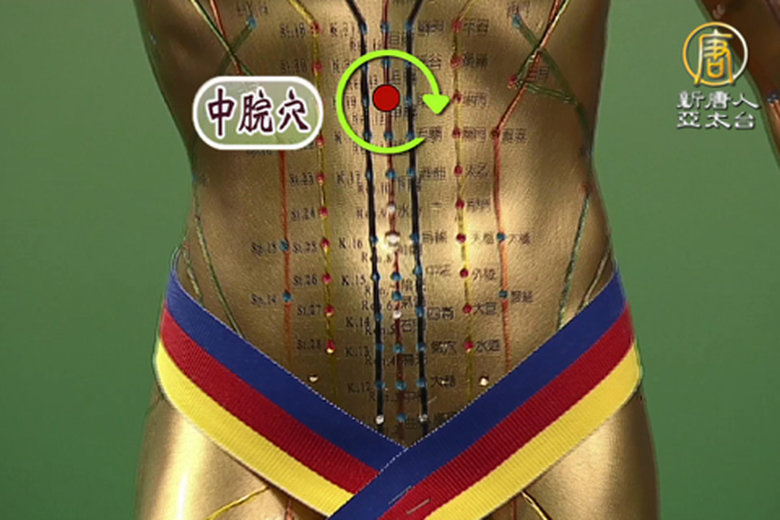

第二單元 胃酸胃痛 按按穴位好輕鬆

中醫除了針灸之外最方便的就是教大家平時按穴位,知道自己的身體哪裡有問題就按哪,沒想到呼吸也是按摩的一種方式,除了足三里啊、內關穴啊、吐納呼吸法是一種內臟按摩耶!不要再亂吃成藥啦~調理好自己的呼吸節奏也能很輕鬆